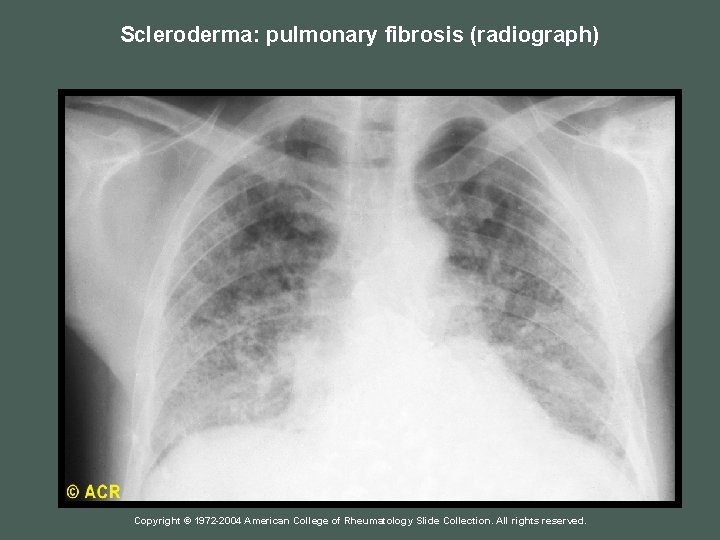

Lungs Interstitial lung disease - Dyspnea - Pleurisy Chest –x-ray: reticular pattern of linear, nodular and line nodular densities "lower two –thirds" - Subnormal diffusing capacity Copyright © 1972 -2004 American College of Rheumatology Slide Collection. All rights reserved.

Scleroderma: pulmonary fibrosis (radiograph) Copyright © 1972 -2004 American College of Rheumatology Slide Collection. All rights reserved.